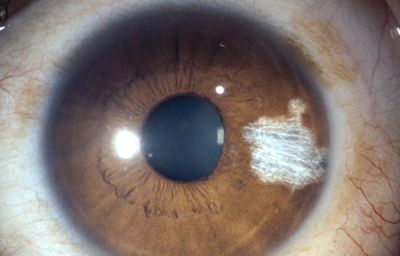

En la cara Anterior esta el pigmento que le da el color al Iris y dependiendo del grado de reabsorción u atrofia de esa capa anterior se pueden observar:

Las Criptas de Fuchs: que son pequeñas aberturas alrededor del collarete, producto de la atrofia o reabsorción de la hoja anterior del iris, que le permiten al estroma y a los tejidos mas profundos estar en contacto con el humor acuoso.

Cuando el Iris no tiene criptas, se considera que la reabsorción u atrofia de la hoja anterior (memb. pupilar) se detuvo en el circulo menor.

En la cara Posterior se ven pliegues radiales muy finos que se extienden desde el margen pupilar hasta el collarete ( miden ± 1.0 mm), y son conocidos como Pliegues radiales de contracción de Schwalbe. Existen ademas los llamados Pliegues estructurales de Schwalbe que son mas gruesos y mas distanciados en la porción ciliar de la cara posterior

La vascularización proviene de las arterias ciliares largas y las ciliares anteriores, que penetran formando una malla radial en el estroma iridiano.

Existe el círculo vascular mayor del Iris situado en la periferia que ya es estroma del cuerpo ciliar, y el círculo menor en el collarete.

Histologicamente son arteriolas, capilares y vénulas con características especiales: no tienen lamina elástica pero si una túnica adventicia que les da el aspecto de un tubo dentro de un tubo, cuya finalidad podría ser protegerlas de acodamientos y posible obstrucción, en el movimiento de dilatación.

Otra característica importante es que los capilares son continuos, no tienen fenestraciones evitando así que macromoléculas sanguíneas plasmáticas, pudieran pasar al estroma iridiano; la cantidad de proteínas derivadas del plasma que están en el humor acuoso es el 1% respecto al encontrado en el plasma en condiciones de normalidad, un mayor porcentaje causaría dispersión de la luz en la cámara anterior y degradaría la calidad de la visión. En la inervación del estroma iridiano hay fibras nerviosas mielinizadas y otras que no lo están. Tiene fibras simpáticas, parasimpáticas y también sustancia P inmuno-reactíva sensorial, que llegan a través de la división oftalmica del V par.1